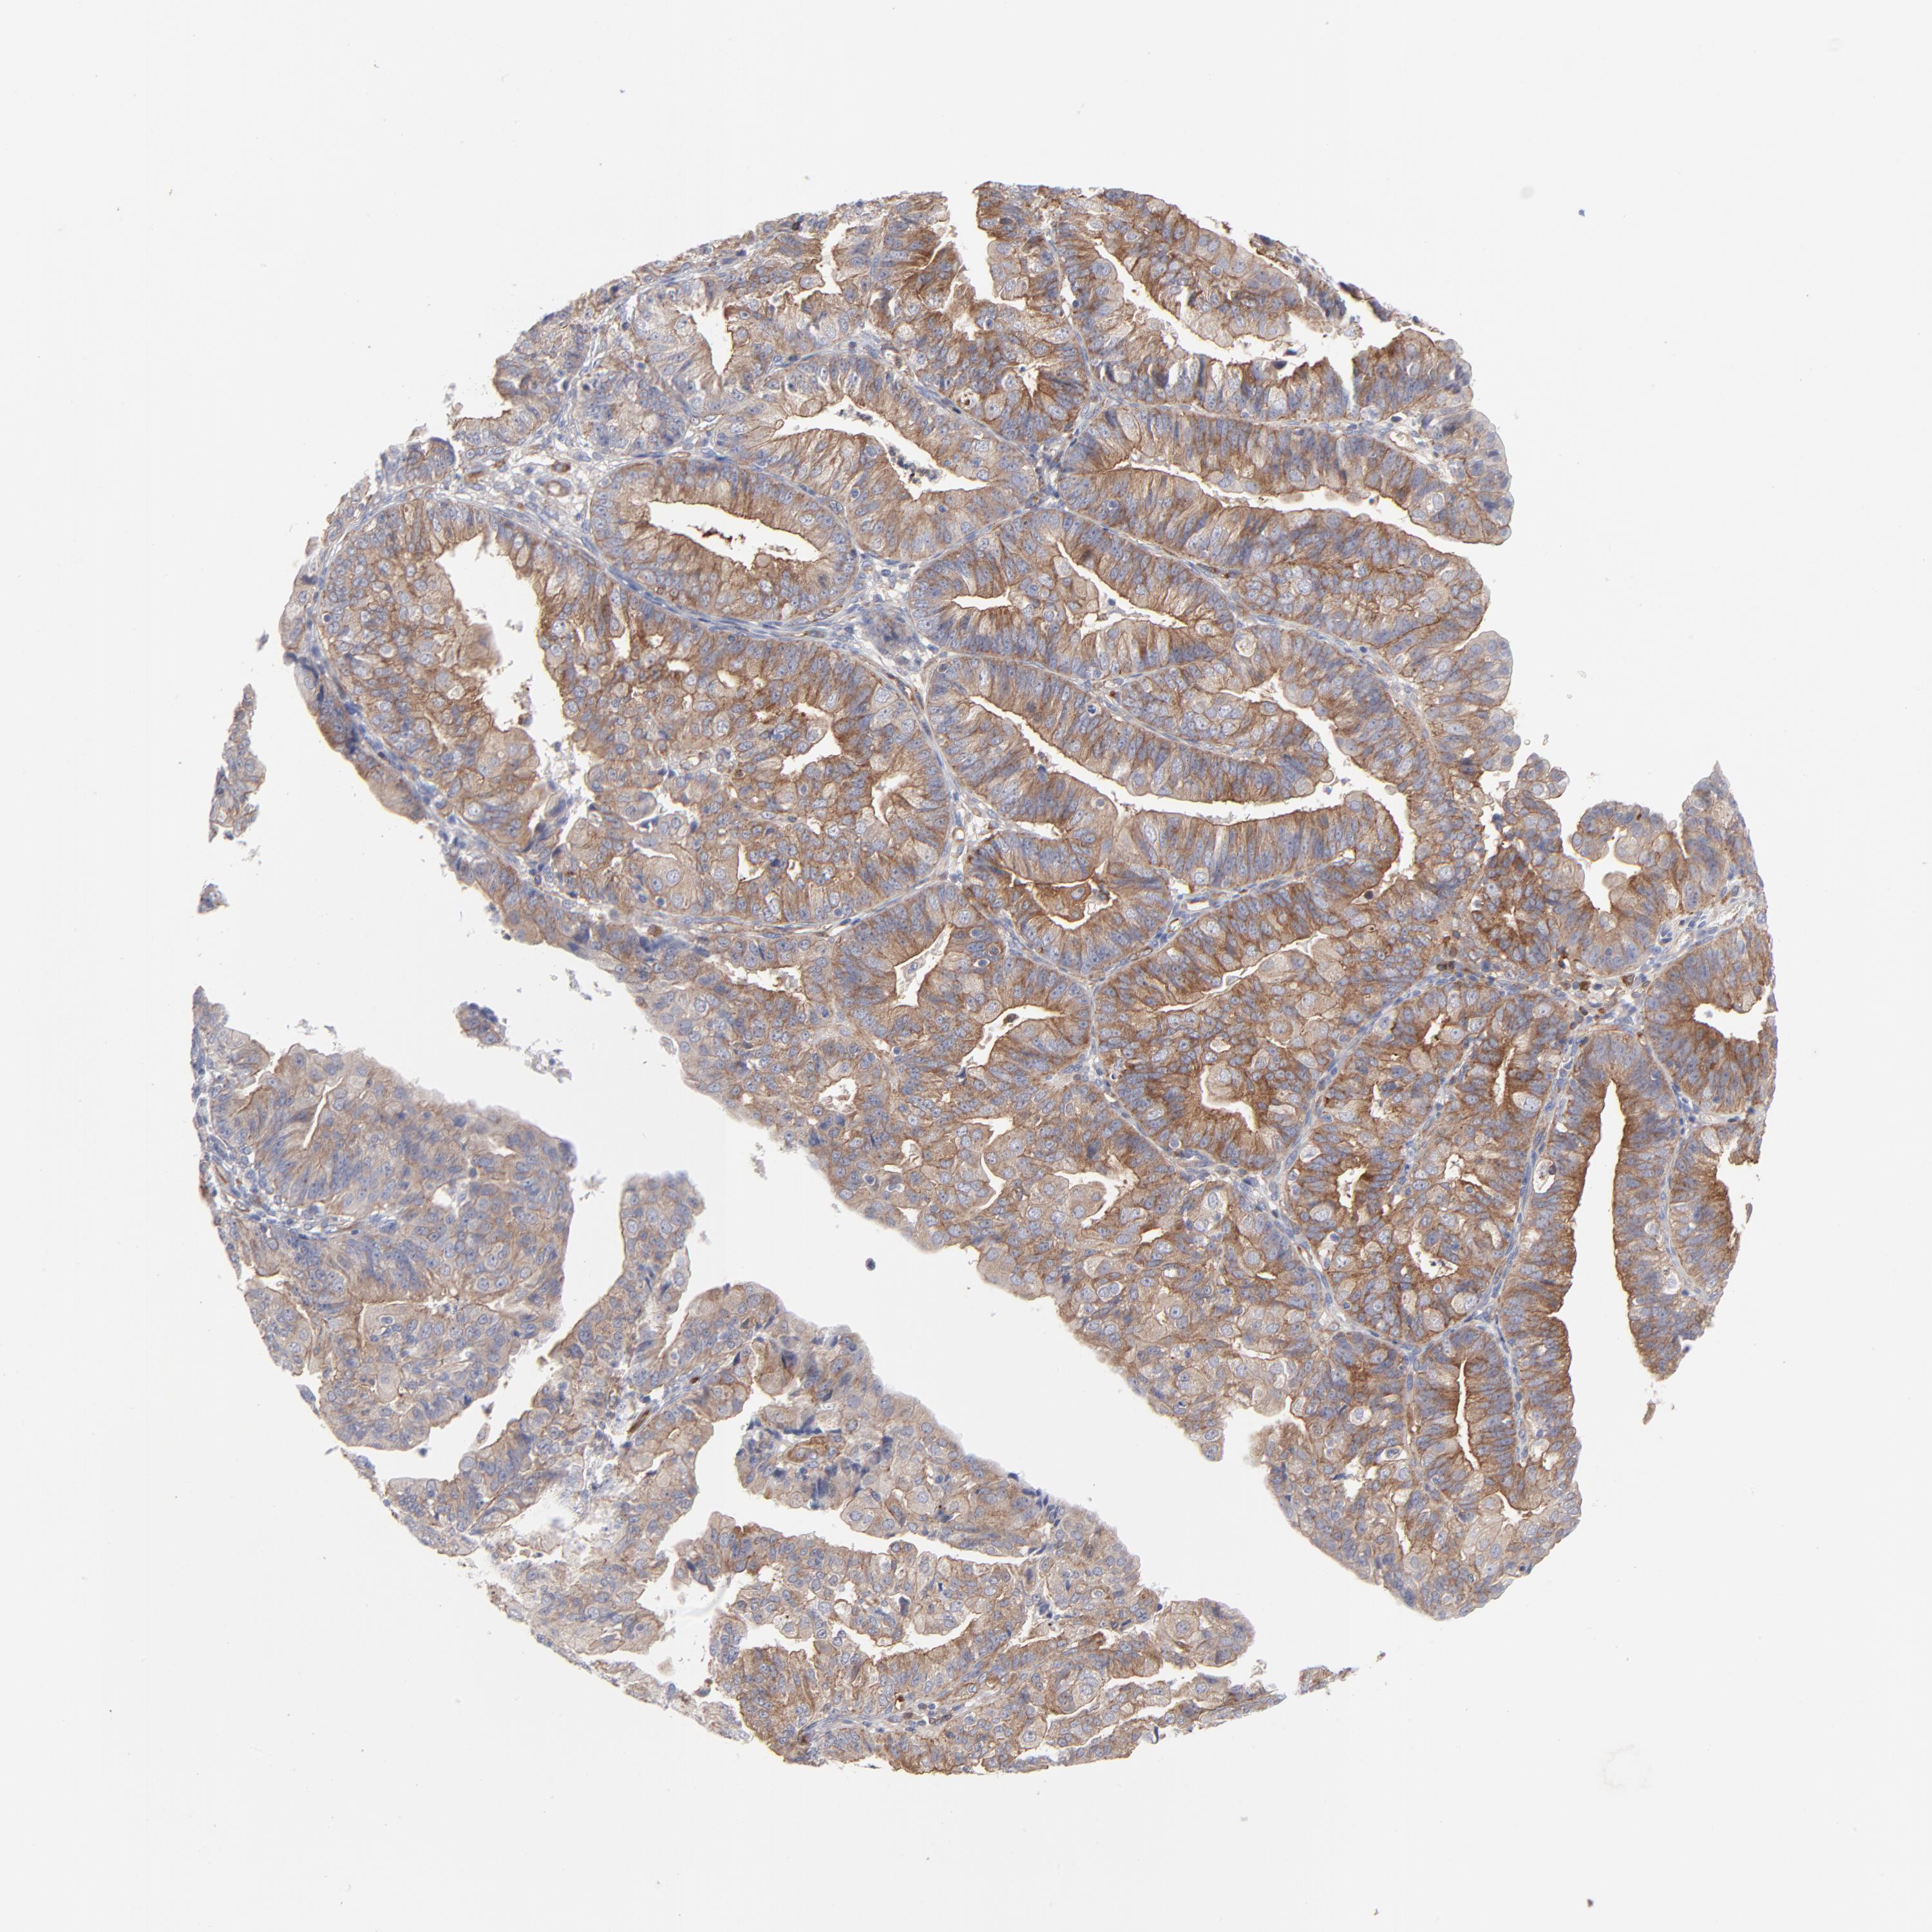

ENDOMETRIAL CANCER - Protein expressioni

A mouse-over function shows sample information and annotation data. Click on an image to view it in a full screen mode. Samples can be filtered based on level of antibody staining by selecting one or several of the following categories: high, medium, low and not detected. The assay and annotation is described here.

Note that samples used for immunohistochemistry by the Human Protein Atlas do not correspond to samples in the TCGA dataset.

Antibody stainingi

Antibody staining in the annotated cell types in the current human tissue is reported as not detected, low, medium, or high, based on conventional immunohistochemistry profiling in selected tissues. This score is based on the combination of the staining intensity and fraction of stained cells.

Each image is clickable and will lead to virtual microscopy that enables deeper exploration of all samples and also displays staining intensity scores, fraction scores and subcellular localization as well as patient and tissue information for each sample.

Antibody CAB003841

Staining

High

Medium

Low

Not detected

Intensity

Strong

Moderate

Weak

Negative

Quantity

>75%

75%-25%

<25%

None

Location

Nuclear

Cytoplasmic/membranous

Cytoplasmic/membranous,nuclear

Adenocarcinoma, NOS